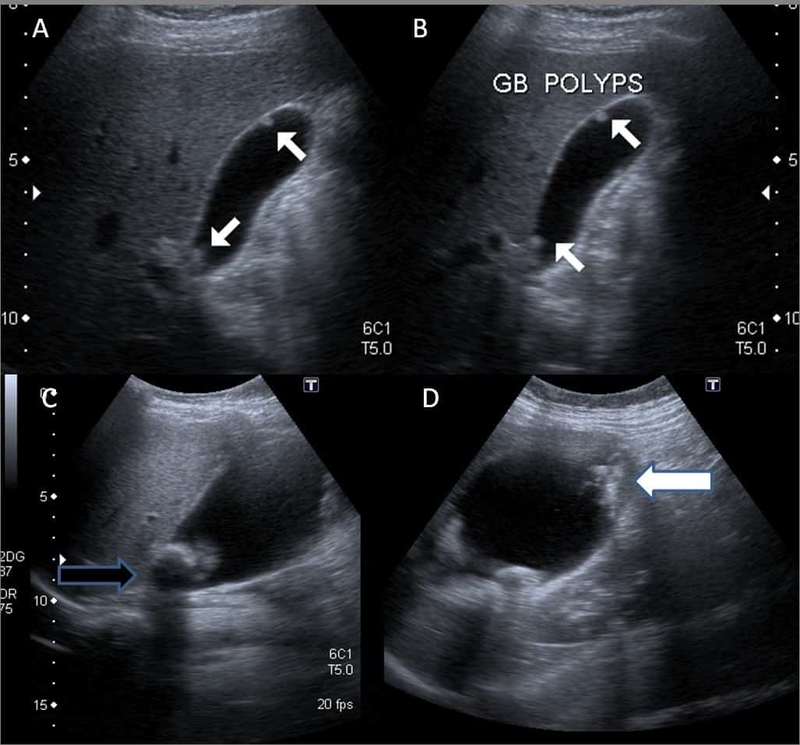

Các khối u lành tính trên thành túi mật biểu hiện dưới dạng polyp túi mật. Mặc dù thường không nguy hiểm nhưng những khối u này có thể gây ra triệu chứng khó chịu nhẹ, đặc biệt là trong bữa ăn.

Hiện nay, mặc dù có nhiều phương pháp chẩn đoán hình ảnh giúp bác sĩ chuyên khoa có thể đánh giá tình trạng sức khỏe túi mật lẫn đường mật trong và ngoài gan, nhưng siêu âm vẫn là biện pháp được đánh giá cao, ưu tiên sử dụng nhờ ưu điểm dễ thực hiện, an toàn, giá thành rẻ cũng như có độ nhạy cao. Thông qua siêu âm, viêm túi mật cấp và các biến chứng của bệnh sẽ được chẩn đoán một cách nhanh chóng.

Cụ thể, siêu âm giúp xác định viêm túi mật cấp khi kích thước túi mật to (đường kính ngang túi mật > 4cm, thành dày > 3mm), quanh túi mật có dịch, đồng thời còn có những dấu hiệu gián tiếp, điển hình như dấu hiệu Murphy siêu âm dương tính, dòng chảy tăng trên siêu âm Doppler màu,...

Bên cạnh đó, phương pháp siêu âm còn có thể xác định nguyên nhân lẫn biến chứng của tình trạng viêm túi mật cấp, bao gồm sỏi túi mật, sỏi đường mật, viêm đường mật hay viêm tụy cấp kèm theo,...